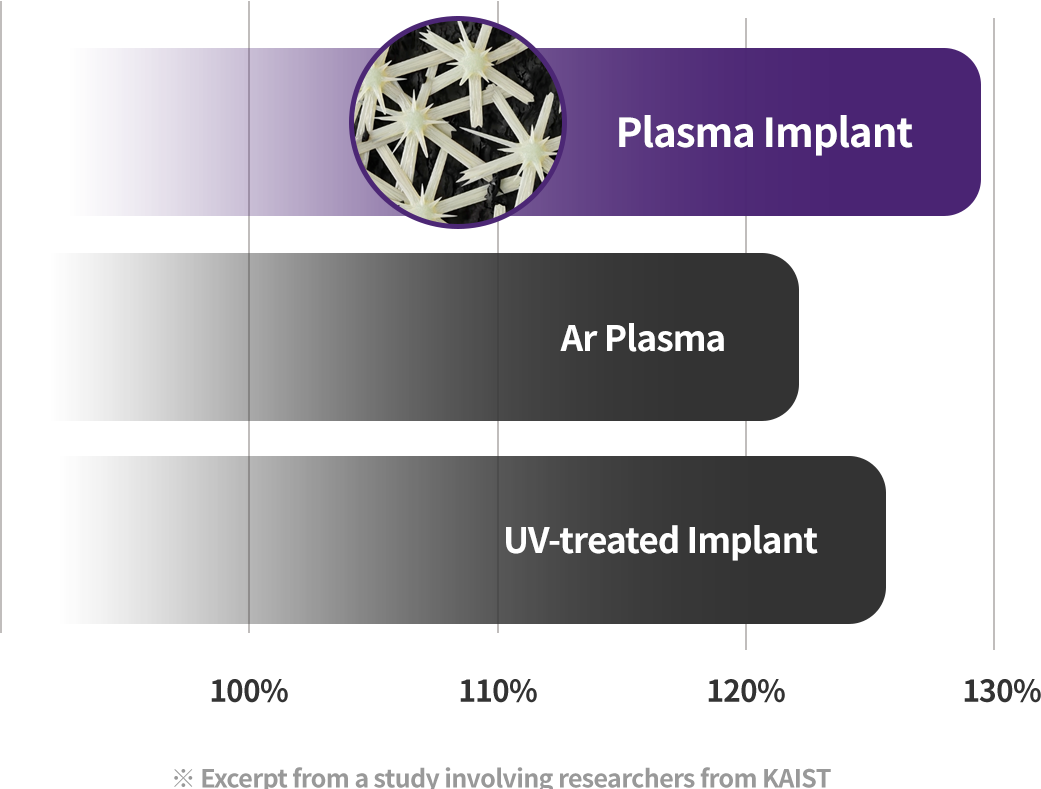

1.7x Higher Bone Integration

Compared with conventional implants, plasma implants showed about 1.7 times higher bone integration within 4 weeks. (Based on 4-week follow-up of actual patients)

Faster Bone Integration

Plasma cleaning activates the surface → faster bone bonding → shorter recovery

Better Biocompatibility

Plasma treatment improves surface hydrophilicity → promotes blood and protein adhesion → an implant the body accepts more easily

Plasma treatment helps remove impurities left on the implant surface and improves surface hydrophilicity for better biocompatibility. Thanks to these benefits, plasma technology helps improve implant success and serves as a key factor for faster recovery.

Improved early protein attachment through organic removal and surface activation